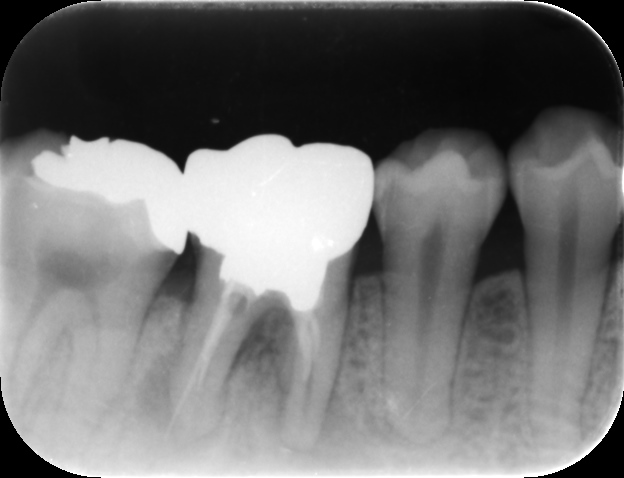

| 治療前レントゲン | 治療前CT |

|---|---|

| 治療前レントゲン |

|---|

| 治療前CT |

根管充填後レントゲンおよびCT画像です。

症状が消失したため、ガッタパーチャとバイオセラミックシーラーにて根管充填を行いました。炎症が強かったため、歯槽骨の吸収の範囲が術前よりも広がっています(矢印)。